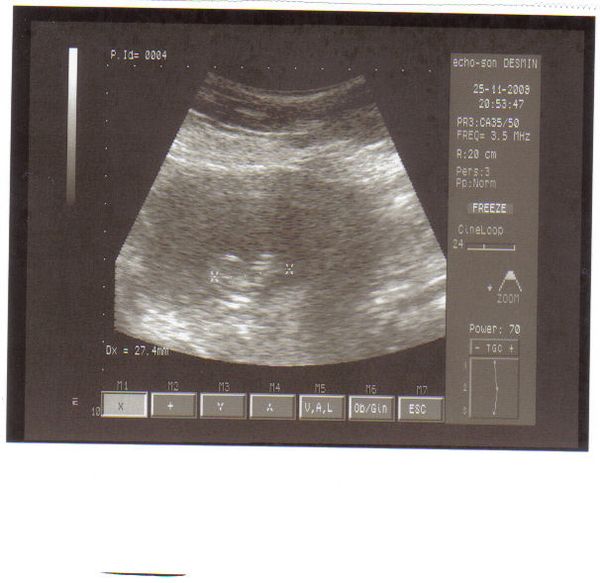

Megjöttem a dokitól, minden rendben van, méhszájam teljesen zárt, babszemjankóm 27,4 mm hosszú és gyönyörűen ver a szívecskéje.Olyan jó volt látni, hiába 4. gyermek, az uh mindig egy nagy élmény.

Úgy néz ki, hogy a méhlepény most a hátsó falon tapad, ami jó is(bár még változhat) mert elől van a császáros heg.

Kaptam képet is, de nem valami jó a gépe, így nem sok minden látszik rajta. Bal oldalon van a buksi kezdemény, és jobbra pedig lesznek a végtagok. Ő már látta a végtagkezdeményeket(én nem), de majd 2 hét múlva a kórházi szuper gépen már szupi képet fogok hozni.

Íme "kid number 4" Laughing Laughing Laughing